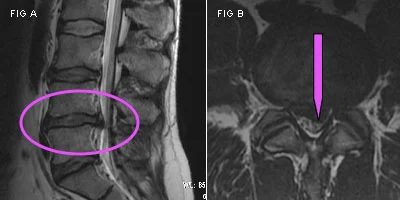

Mri Disc Herniation Herniated Discs From Car Accidents

Herniated Discs From Car Accidents

A 32year Old Male Comes With Spine Injury Following Motor Car Accident Download Scientific Diagram